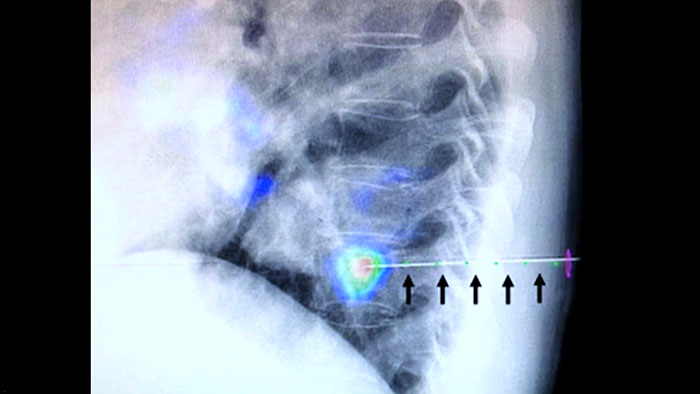

O XperGuide fornece uma orientação de imagem em tempo real altamente precisa de cada agulha para uma posição alvo, sobrepondo trajetórias pré-planeadas com imagiologia fluoroscópica.3